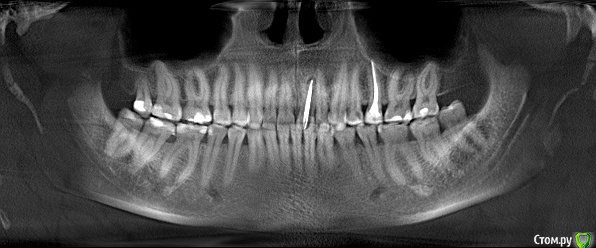

barvika Опубликовано 21 сентября, 2016 Поделиться Опубликовано 21 сентября, 2016 Здравствуйте. Для решения вопроса по имплантации 21 зуба по старым штифтом и гранулемой было сделано КТ. Доктор на КТ кроме этого зуба ничего критичного не увидел. Но я, внимательно рассмотрев снимок, заметила светлое пятно под 1ым моляром слева. Приблизительно на этом месте в самой ротовой полости на десне маленький твердый выступ, немного острый, размером не более 1 мм.Обратила внимание хирурга на это пятно, он рассмотрел, сказал , что его видно только на орто, в 3d не видно,что сама кость ровная. Вообщем, обнадежил меня ,что ничего страшного, просто уплотнение кости и ничего с этим делать не надо, только повторить КТ через год. Но я еще тот паникер, уже накрутила себя.Снимки приложила, есть еще на диске само КТ, но не знаю, какие файлы из него нужно выложить.Посмотрите, пожалуйста. Спасибо. Ссылка на комментарий

barvika Опубликовано 22 сентября, 2016 Автор Поделиться Опубликовано 22 сентября, 2016 Спасибо Вам! Только я просчиталась, пятно под первым моляром на нижней челюсти слева. Прошу прощения за ошибку. Ссылка на комментарий

red_butler Опубликовано 22 сентября, 2016 Поделиться Опубликовано 22 сентября, 2016 Спасибо Вам! Только я просчиталась, пятно под первым моляром на нижней челюсти слева. Прошу прощения за ошибку.приглядитесь, справа тоже есть, считайте это "родимыми пятнами" Ссылка на комментарий